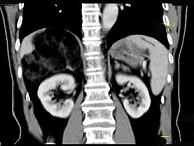

问题 男,59岁,右侧腰背酸痛,CT检查如图所示,应诊断为 ( )

选项 A、右腹膜后脂肪瘤 B、右肾血管平滑肌脂肪瘤 C、右肾上腺转移瘤 D、右肾上腺髓样脂肪瘤 E、右肾上腺腺瘤

答案 D